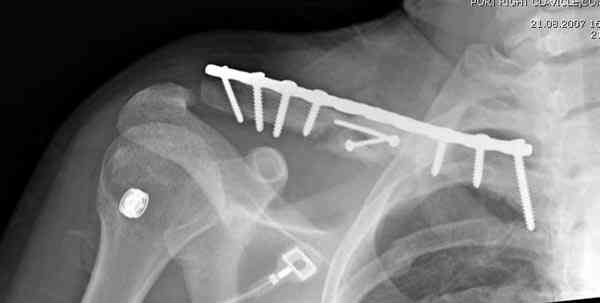

ГГШ> Результат стационарного лечения приведен на рентгенограмме (Xray_3).

Это картинка то есть через неделю после травмы, при выписке? Более чем приемлемо.

Оценка положения костных фрагментов должна осуществляться по рентгенограммам, вы.полненным в двух проекциях. Стандартная ( и почему.то считающейся достаточной в большинстве наших лечебных учреждений) передне.задняя проекция дополняется шейной проекций под уг.лом 45°. Смещения: расхождение в поперечном направлении, отсутствие кортикального контакта, укорочение ключицы более 1,5 см . недопустимы и должны быть устранены (11,12).

Эти принципы в равной степени относятся как к консервативному, так и оперативному ле.чению переломов ключицы. И с позиций этих принципов, вряд ли можно назвать удовлетворительным результат лечения результат <лечения>, при котором:

1. Не выполнена репозиция перелома;

2. Не идет речи не не только о стабильности фиксации, но и даже о контакте между отломками,

3. Гарантирована травматизация мягких тканей в зоне перелома из-за неустраненного смещения и сохранения подвижности отломков;

4. Полноценное восстановление функции ожидается только у 3-х из 4-х леченных таким способом пациентов.